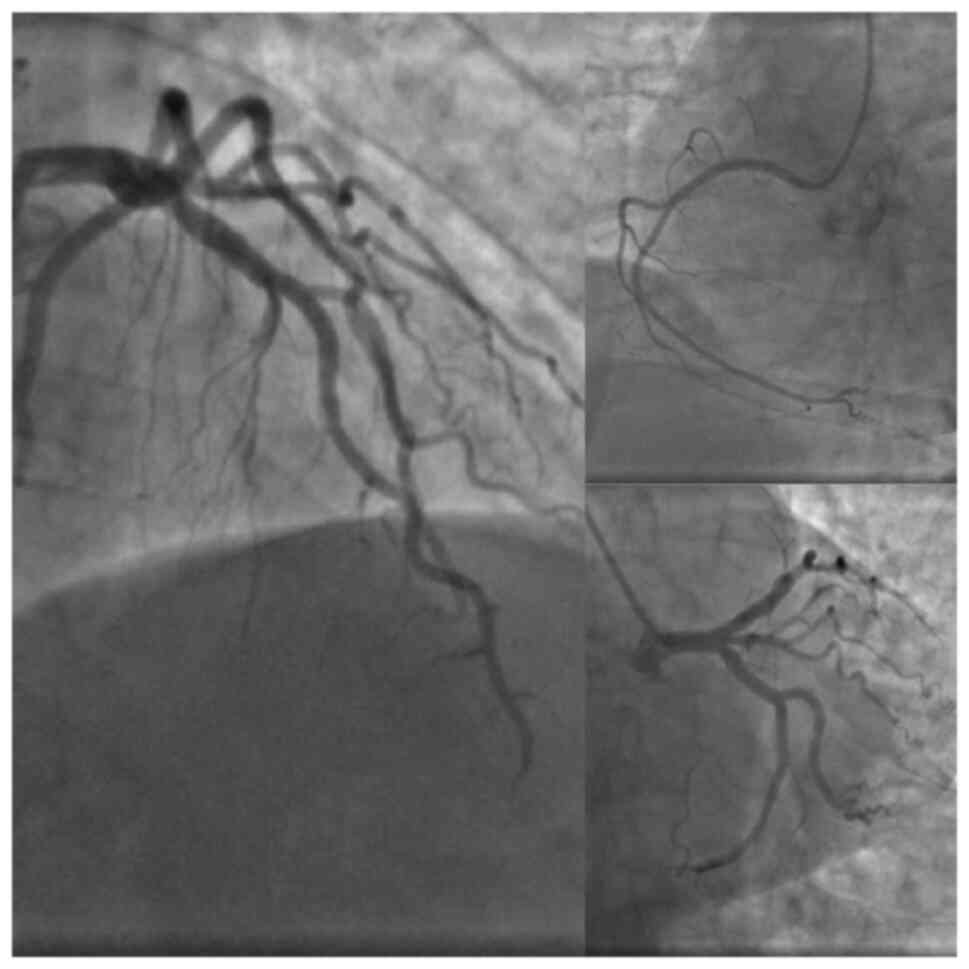

A blood examination was conducted and revealed a normal blood composition. The troponin I test (0.03 ng/ml), renal function and liver function tests were within the normal ranges, while the C-reactive protein (98.80 mg/l) (normal range, ≤5 mg/l) and D-dimer (7599.9 ng/ml) (normal range, ≤500 ng/ml) levels were abnormal. An ECG revealed a biphasic inversion of the T wave in precordial leads in the pain-free interval. A minimal elevation of the ST segment, no precordial Q waves, and one ventricular extrasystole were also observed in the ECG (Fig. 1). The echocardiography revealed a moderate dilatation of the right ventricle, moderate tricuspid regurgitation, inter-ventricular septum flattening (D shape), and positive McConnell's sign. A coronary angiography was performed and this did not reveal any notable findings (Fig. 2). There was no critical stenosis of the proximal LAD coronary artery. A computed tomography pulmonary angiography revealed an acute pulmonary embolism (Figs. 3 and 4). Therefore, all the results supported the occurrence of pseudo-Wellens syndrome. The Thrombolysis in Myocardial Infarction (TIMI) score was equal to one and revealed a low risk of adverse cardiac issues (Table I). The score was determined by the occurrence of only a marked change in her ECG scan.

Figure 2

Coronary angiography through right radial access indicates a co-dominant system with no significant coronary lesions.